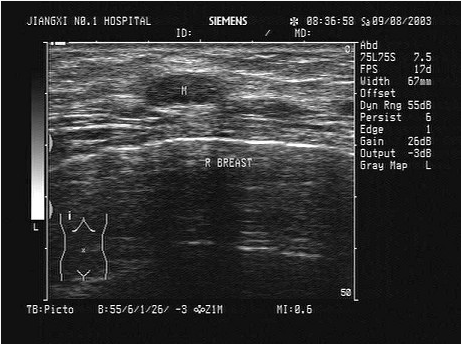

某患者自诉乳腺可触及一包块,光滑可移动,超声图像如图,诊断为()。